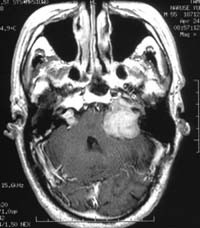

<³úÁ¤µ¿¸Æ±âÇü>

½Ã»óµ¿

ÀÎÁ¢ºÎ ºÎÀ§ÀÇ ³úÁ¤µ¿¸Æ±âÇüÀÇ MRI¿Í Ç÷°üÁ¶¿µ¼ú

¼Ò°ß